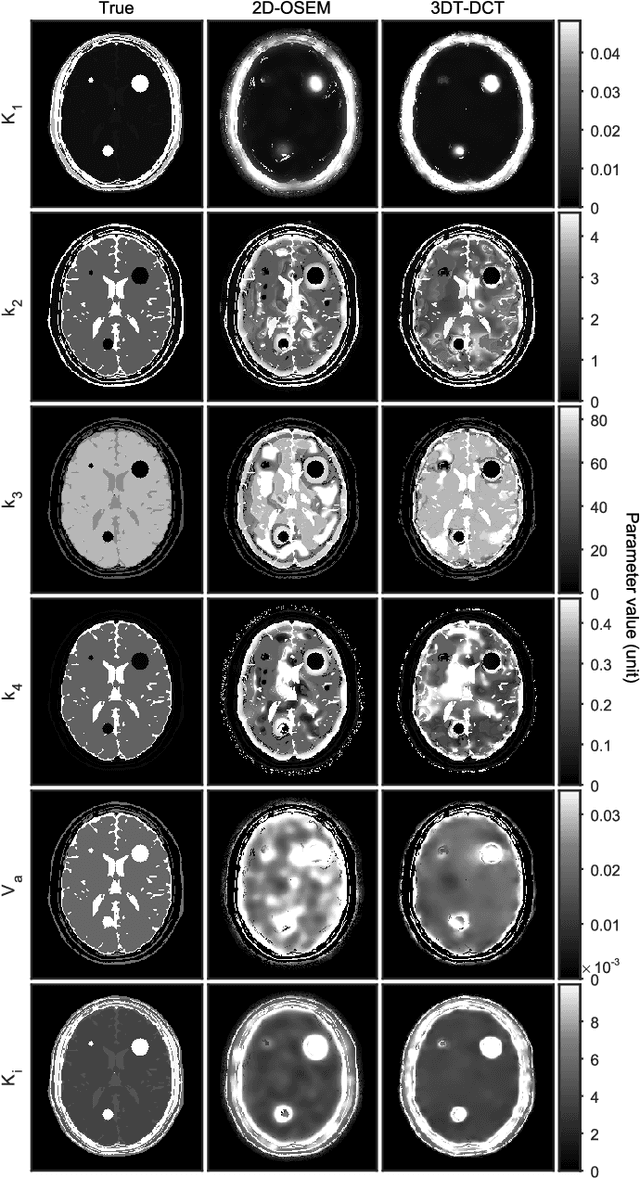

Abstract:Our aim was to enhance visual quality and quantitative accuracy of dynamic positron emission tomography (PET)uptake images by improved image reconstruction, using sophisticated sparse penalty models that incorporate both 2D spatial+1D temporal (3DT) information. We developed two new 3DT PET reconstruction algorithms, incorporating different temporal and spatial penalties based on discrete cosine transform (DCT)w/ patches, and tensor nuclear norm (TNN) w/ patches, and compared to frame-by-frame methods; conventional 2D ordered subsets expectation maximization (OSEM) w/ post-filtering and 2D-DCT and 2D-TNN. A 3DT brain phantom with kinetic uptake (2-tissue model), and a moving 3DT cardiac/lung phantom was simulated and reconstructed. For the cardiac/lung phantom, an additional cardiac gated 2D-OSEM set was reconstructed. The structural similarity index (SSIM) and relative root mean squared error (rRMSE) relative ground truth was investigated. The image derived left ventricular (LV) volume for the cardiac/lung images was found by region growing and parametric images of the brain phantom were calculated. For the cardiac/lung phantom, 3DT-TNN yielded optimal images, and 3DT-DCT was best for the brain phantom. The optimal LV volume from the 3DT-TNN images was on average 11 and 55 percentage points closer to the true value compared to cardiac gated 2D-OSEM and 2D-OSEM respectively. Compared to 2D-OSEM, parametric images based on 3DT-DCT images generally had smaller bias and higher SSIM. Our novel methods that incorporate both 2D spatial and 1D temporal penalties produced dynamic PET images of higher quality than conventional 2D methods, w/o need for post-filtering. Breathing and cardiac motion were simultaneously captured w/o need for respiratory or cardiac gating. LV volumes were better recovered, and subsequently fitted parametric images were generally less biased and of higher quality.